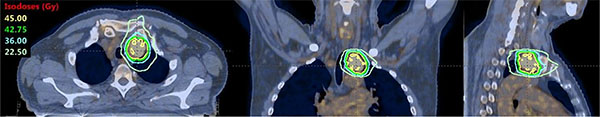

All patients underwent contrast-enhanced 4 DCT scan and FDG-CT PET for target definition and treatment preparation. All patients were immobilized in supine position with thermoplastic masks. No respiratory gating nor breath control systems were used. Target and critical structures were outlined per each individual patient. The clinical target volume (CTV) included the metastatic lymph node and was delineated as ITV (internal target volume) on the 4DCT images. A margin of 5 mm was added to CTV in all directions to generate planning target volume (PTV). In all cases, critical structures were: lungs, oesophagus/stomach, heart, large vessels, main bronchus/trachea and spinal cord. Dose objectives for these organs are shown in Table 3. The mean (and standard deviation of the mean) PTV volume over the whole patient cohort was 37.1 ± 5.7 cm3. SBRT treatments were delivered with VMAT technology in its RapidArc form, on one of our Varian TrueBeam linear accelerators equipped with either Millennium 120-MLC (5 mm leaf width) or HD-120 MLC (2.5 mm leaf width); the beam energy was 10 MV with FFF (flattening filter free) mode, allowing a maximum dose rate of 2400 MU/min. The arc arrangement was with two partial arcs (160 to 220 degree each) avoiding the entrance through the contralateral side to keep the dose bath as low as possible. Treatment planning was performed on Varian Eclipse system version 11: optimization process used the Progressive Resolution Optimizer algorithm (PRO3, version 11), and the dose distribution was computed with the AAA (Anisotropic Analytical Algorithm, version 11) photon dose calculation algorithm, with a calculation grid of 1.5 mm. An example of dose distribution is shown in Figure 3.

Figure 3: Example of dose distribution of a SBRT plan in a patient presenting primary lung tumor, two nodal metastases, para-aortic and thoracic. Here the thoracic treatment plan of 45 Gy in 6 fractions.

Patients were treated with SBRT with different fractionation scheme according to nodal site and number, organs at risk proximity and previous mediastinal irradiation. Prescribed schedules were 45 Gy in 6 fractions, 48 Gy in 6 fractions, 60 Gy in 8 fractions, 30 Gy in 5 fractions, 36 Gy in 6 fractions and 40 Gy in 5 fractions.